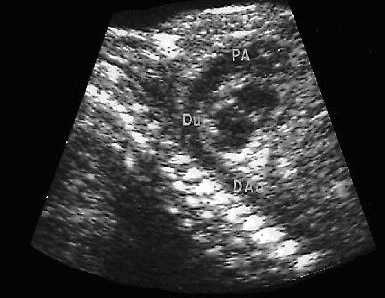

¿Qué es un ecocardiograma fetal?

El ecocardiograma fetal lo realiza un cardiólogo pediatra . El examen puede hacerse utilizando una ecografía abdominal o transvaginal.

Durante el examen, la sonda del transductor se mueve para obtener imágenes de diferentes áreas y estructuras del corazón fetal. Entre las técnicas que a veces se utilizan para obtener información detallada sobre el corazón del feto se incluyen las siguientes:

La ecocardiografía fetal puede ayudar a detectar anormalidades cardiacas fetales antes del nacimiento permitiendo una intervención médica o quirúrgica más rápida una vez que el bebé nace. Esto aumenta las probabilidades de supervivencia de los bebés con un defecto cardiaco grave luego del parto.

- Ecografía abdominal. Se aplica gel sobre el abdomen y se desliza un transductor de ultrasonido sobre el gel para crear la imagen.

- Ecografía transvaginal. Se inserta un pequeño transductor de ultrasonido pequeño dentro de la vagina, el cual se coloca contra la parte posterior de la misma para crear las imágenes. La ecografía transvaginal produce imágenes más nítidas que la ecografía abdominal y se suele usar al comienzo del embarazo.

- Ecocardiografía 2-D (bidimensional). Esta técnica se utiliza para observar las estructuras reales del corazón y su movimiento. La imagen de la eco 2D aparece en el monitor en forma de cono, pudiéndose observar el movimiento de las estructuras del corazón en tiempo real. Esto le permite al médico ver las diversas estructuras del corazón en funcionamiento para poder así evaluarlas.

- Ecocardiografía Doppler. Se utiliza para medir y evaluar el flujo de sangre a través de las cavidades y las válvulas del corazón. La cantidad de sangre que se bombea con cada latido es una indicación del funcionamiento del corazón. Además, el eco Doppler puede detectar un flujo de sangre anormal en el interior del corazón, lo que indicaría problemas como una abertura entre sus cavidades, el mal funcionamiento de una o más de las cuatro válvulas cardiacas, o un deterioro en las paredes del corazón.

- Doppler en color. Es una forma mejorada de la ecocardiografía Doppler. En el Doppler en color se utilizan diferentes colores para indicar las distintas direcciones del flujo de la sangre. Esto simplifica la interpretación de las imágenes.